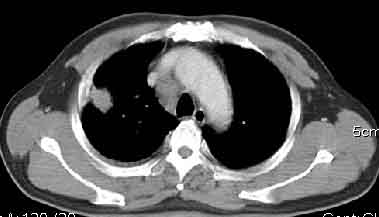

该病例我的诊断意见:右肺上叶周围型肺癌伴纵隔和右肺门淋巴结增大和右肺上叶阻塞性肺炎{病灶周围致密影以近肺门侧明显!}。右侧少量胸腔积液。

一. 1)症状有无发热及慢性过程.2)化验室检查?3)有无tb接触史?二.右肺上叶见片团状影,边界欠清,外侧方见一结节状软组织影,密度欠均匀,内可见低密度坏死区.周围强化明显,肺内见纤维索条影,局部胸膜增厚,但无明确胸膜凹陷.上叶支气管壁增厚,肺门及纵隔淋巴结增大.右侧胸腔少量积液.诊断意见:1右肺上叶慢性感染性疾病(肺tb?)伴肺门,纵隔淋巴结大.右胸少量积液.右肺上叶结节影多为tb球?2右肺上叶周围型肺ca伴肺门,纵隔淋巴结转移待排.右肺上叶炎变(肺门及纵隔淋巴结压迫).右胸少量积液.等待随返结果.